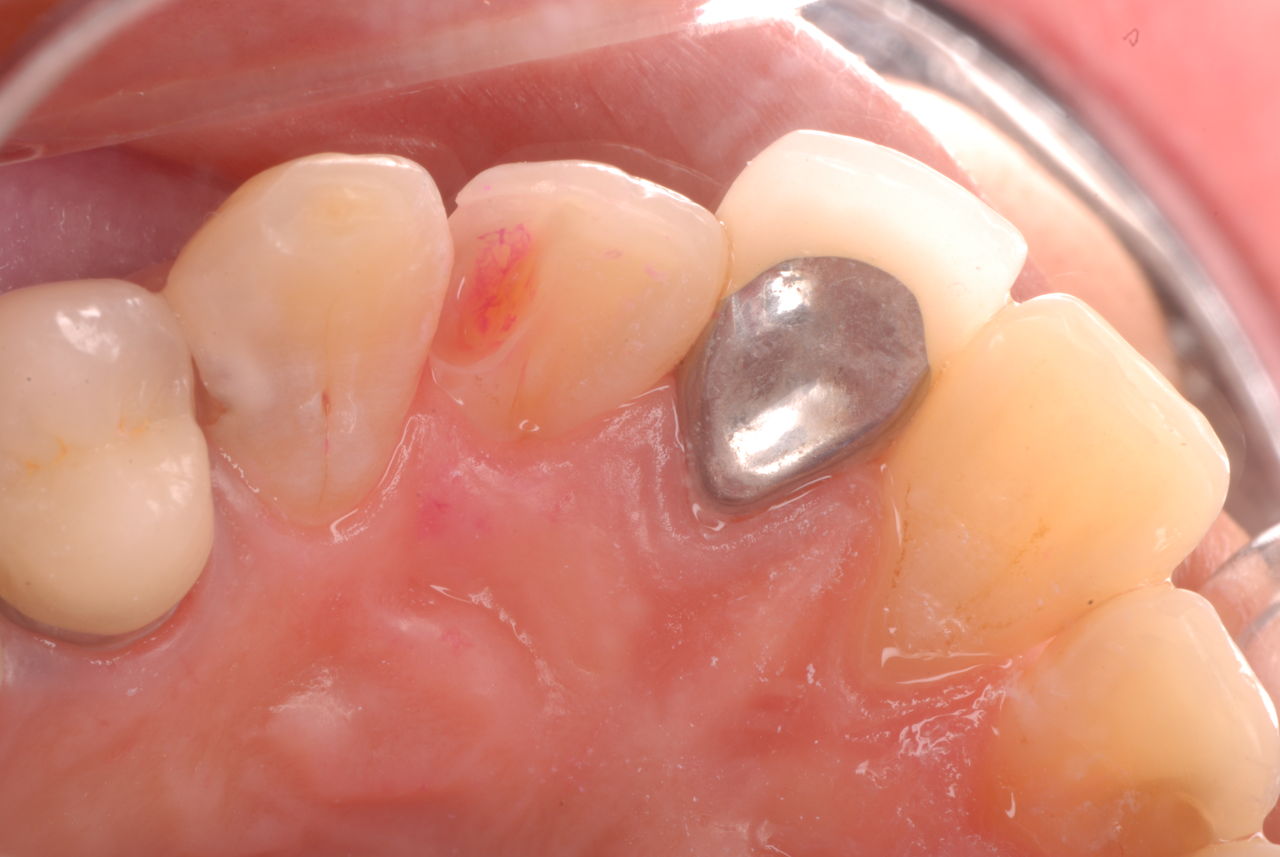

色々不満な入れ歯です。

発音や見える金属が気になるようです。

ご自分でやられても歯茎から血が出ないと話をされていましたが、私がブラシを当てると悲惨な状態であることがわかりました。